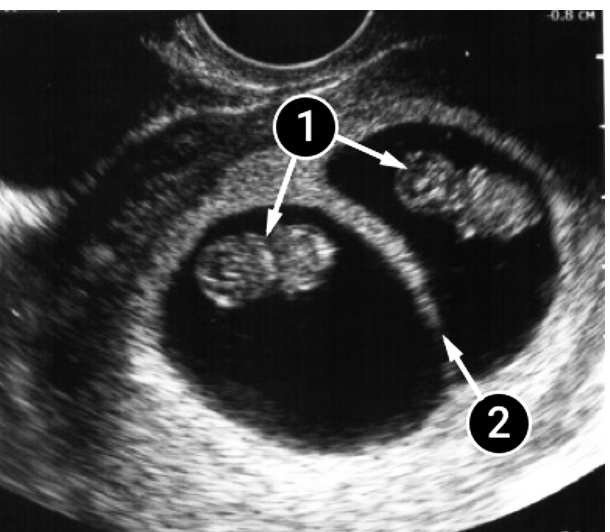

La siguiente foto muestra a dos bebés separados entre sí por un tabique amniótico. Cada uno de los dos pequeños tiene su propia cavidad amniótica y su propio líquido amniótico.

La placenta de ambos es compartida y se encuentra directamente sobre los sacos fetales a lo largo de la pared frontal del útero.

Los cuerpos de los gemelos son claramente visibles, tienen cabezas grandes y cuellos pequeños (completamente normal en esta semana de gestación). En el bebé del lado derecho de la imagen, puedes ver su manita.

- Dos bebés.

- Tabique amniótico.